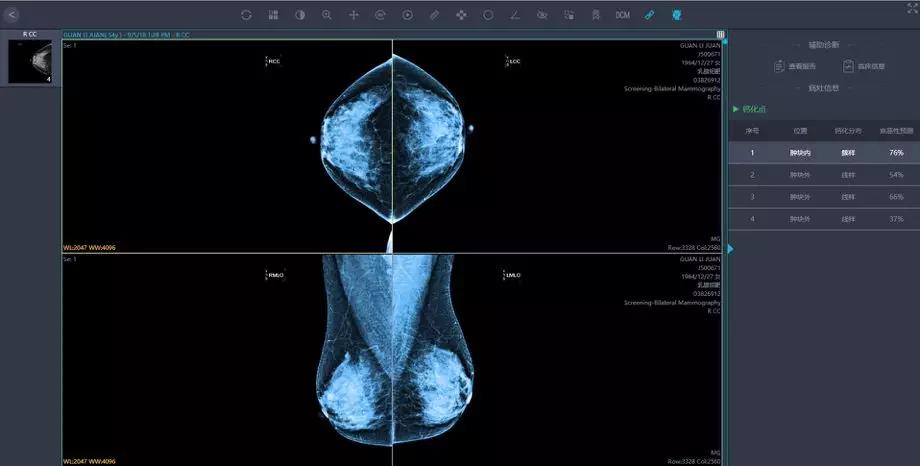

将这些影像学及临床资料汇集,就为人工智能技术提供了大数据基础。人工智能的影像识别和深度学习能力,能够帮助医生筛除正常影像,着重标注疑似病灶的区域,让影像科医生审片更加精准高效。

人工智能在影像识别的速度上胜于人工操作,同时也有利于临床医生制定针对性的治疗方案, 特别对于偏远地区和基层医生而言,这一技术的应用更加意义重大。

汇医慧影公司曾在胸部结节,神经系统,甲状腺等多器官系统影像与国内外顶级医院的影像及专科医生进行过人机读片对比,经过深度学习的人工智能系统,读片准确率达到90%。

英特尔至强服务器可将深度网络模型优化并将数据集进一步加强,也将会继续帮助提高该识别准确率,其对数据的分析和比较“眼力”,早已突破人类极限,达到医疗影像辨识的新高度。